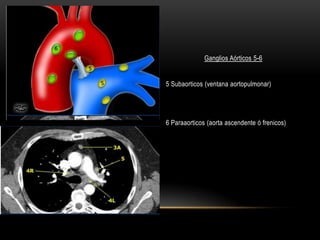

Ganglios Aórticos 5-6

5 Subaorticos (ventana aortopulmonar)

6 Paraaorticos (aorta ascendente ó frenicos)

Ganglios Aórticos 5-6 5Subaorticos (ventana aortopulmonar) 6 Paraaorticos (aorta ascendente ó frenicos)

• #39 5. SubaorticnodesSubaortic or aorto-pulmonary window nodes are lateral tothe ligamentumarteriosum or the aorta or left pulmonaryartery and proximal to the first branch of the leftpulmonary artery and lie within the mediastinal pleuralenvelope.6. Para-aorticnodesPara-aortic (ascending aorta or phrenic) nodes are locatedanteriorly and laterally to the ascending aorta and theaortic arch from the upper margin to the lower margin oftheaorticarch.